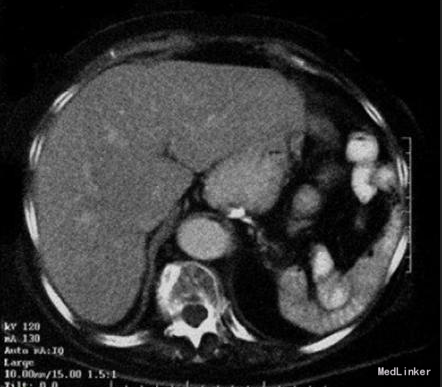

主诉:女性因低热、厌食、腹部不适和左腹胀6个月前来就诊。6个月前的腹部CT扫描显示脾充盈缺损,当时解释为脾脏囊肿,未予特殊治疗。体检发现她有轻度贫血,自诉易疲劳。

查体及辅查 腹部检查可触及脾脏显著增大。未触及外周淋巴结肿大。胸部和纵膈CT扫描除了一些与她的年龄相符的纤维化变化以外未见明显异常。未见纵膈淋巴结肿大。腹部CT扫描发现脾大,有一个明确的肿块,占据约2/3脾脏。